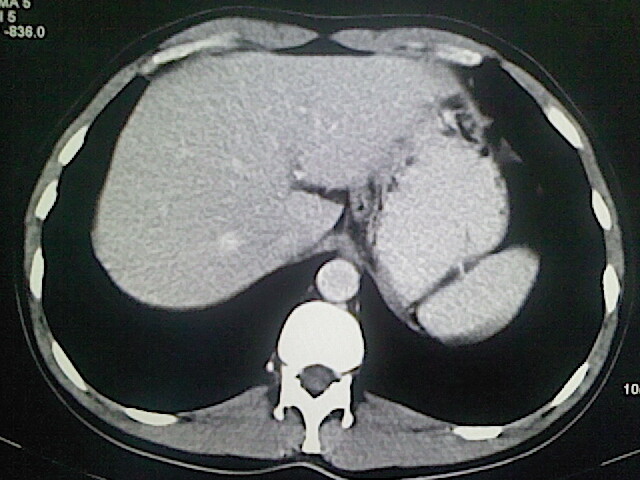

以下是引用卜一在2009-3-14 9:49:00的发言:[br]胆囊萎缩,胆囊壁不规则增厚,内部结构模糊,增强明显强化。另:肝左叶外侧段肝囊肿。支持:慢性胆囊炎!高度可疑:胆囊癌!

以下是引用余辉在2009-3-14 8:48:00的发言:[br]1)慢性胆囊炎。2)肝左叶外侧段肝囊肿。3)脂肪肝。[br]支持,胆囊萎缩,密度增高,不知b超具体有何提示,钙胆汁?结石?

以下是引用jiangjing在2009-3-14 10:18:00的发言:[br]1)慢性胆囊炎。2)肝左叶外侧段肝囊肿。3)脂肪肝。4.】建议行肝功能检查